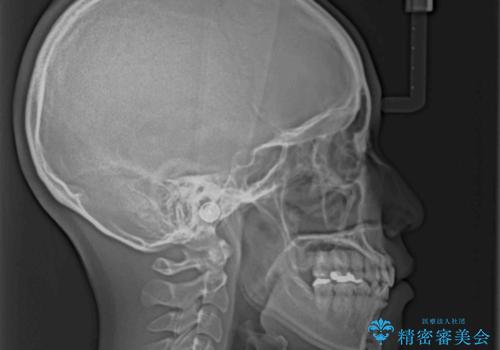

急速拡大とワイヤー抜歯矯正で唇を閉じやすく

- 口元の突出感を気にして来院された患者様です。

デコボコと口元の突出感が認められたため、上下左右の第1小臼歯4本を抜歯してのワイヤー矯正を行うこととしました。

上顎歯列の横幅が狭く、下顎大臼歯の歯軸が舌側に倒れていたため、急速拡大装置により上顎骨を側方に拡大し、咬み合わせを改善することとしました。

上顎歯列幅を拡大したことで、デコボコを容易に解消することができるようになったため、抜歯により得られたスペースを口元の突出感改善に利用することができました。